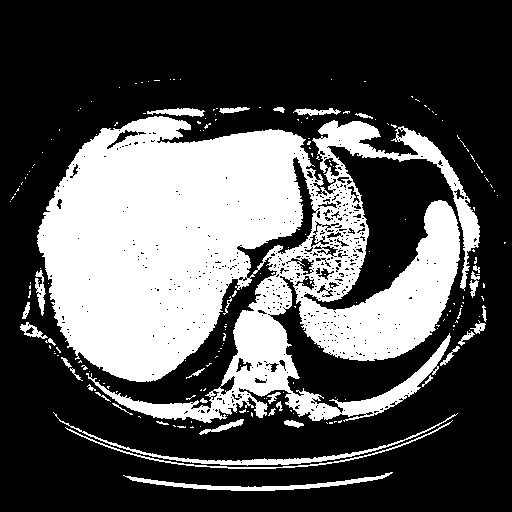

Image Grid

4Γ—3 grid: Rows show different image types (Original NATIVE, Reconstructed NATIVE, Original VENOUS, Generated VENOUS), Columns show windowing techniques (No Window, Lung Window, Mediastinum Window)

Generated VENOUS CT scan (A→B translation)

Full window (WL 1023.5, WW 4095 β†’ Low βˆ’1024, High +3071)

Actual HU range: [-1024.0, 3071.0]

Lung window (WL -600, WW 1500 β†’ Low βˆ’1350, High +150)

Actual HU range: [-1350.0, 150.0]

Mediastinum window (WL 40, WW 400 β†’ Low βˆ’160, High +240)

Actual HU range: [-160.0, 240.0]